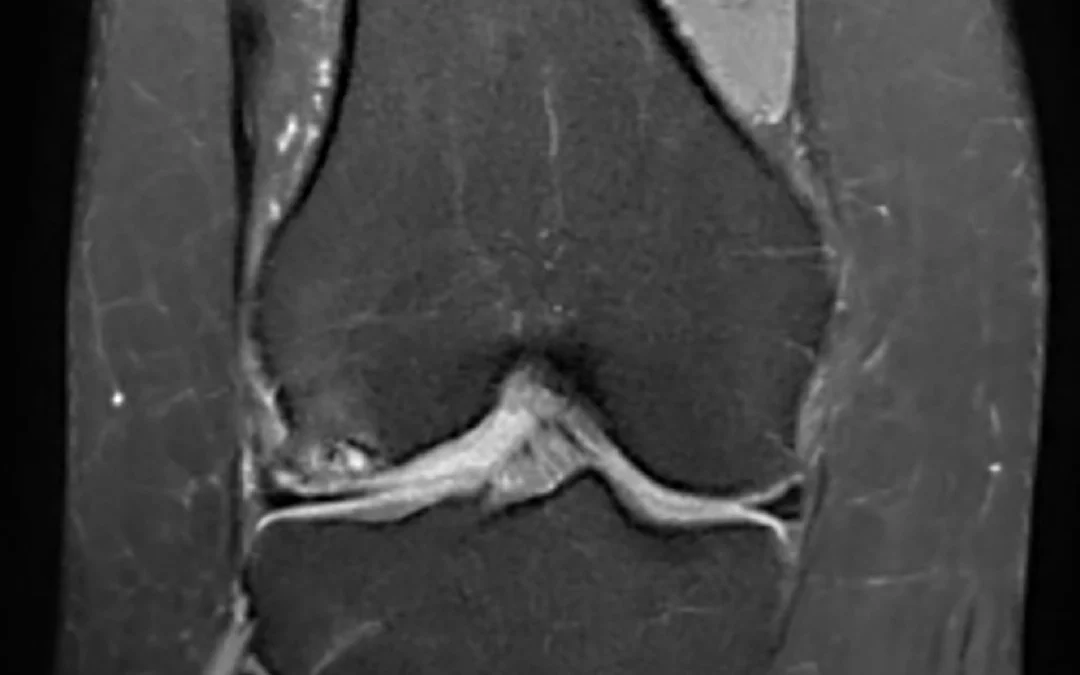

La RM 3T permite obtener imágenes de altísima resolución, con un nivel de detalle superior al de los equipos convencionales. Gracias a ello, se facilita la correcta valoración de estructuras complejas como:

Cartílago

Meniscos

Ligamentos

Tejidos blandos

Esta capacidad de detalle resulta fundamental para detectar lesiones con mayor exactitud y reducir el margen de error diagnóstico.

Estudio de rodilla mediante RM 3 Teslas de VOT, con alta definición anatómica y excelente contraste tisular para una valoración precisa de estructuras osteoarticulares y partes blandas.